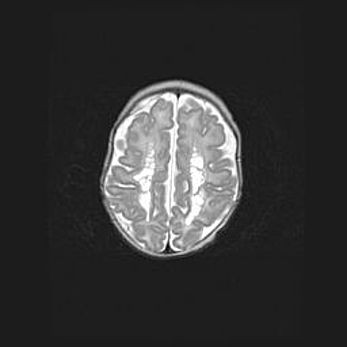

Сообщающаяся гидроцефалия. Кистозная энцефаломаляция головного мозга.

Возраст: 3 месяца 4 дня

Вес: 3100 г

Пол: женский

Окружность головы: 34 см

Срок гестации: 31 неделя

Кистозная энцефаломаляция головного мозга - одна из форм поражения головного мозга в детском возрасте. Характеризуется возникновением множественных и распространённых кист в коре, белом веществе и подкорковых образованиях головного мозга у плодов, новорождённых и детей раннего возраста. Развитие кистозной энцефаломаляции связано с внутриутробной асфиксией и гипотонией, родовой травмой, тромбозом синусов, пороками развития сосудов, инфекциями, сепсисом и другими причинами. Наиболее значимые инфекционные агенты: вирусы простого герпеса, цитомегалии, краснухи, токсоплазмы, энтеробактерии, золотистый стафилококк и другие.